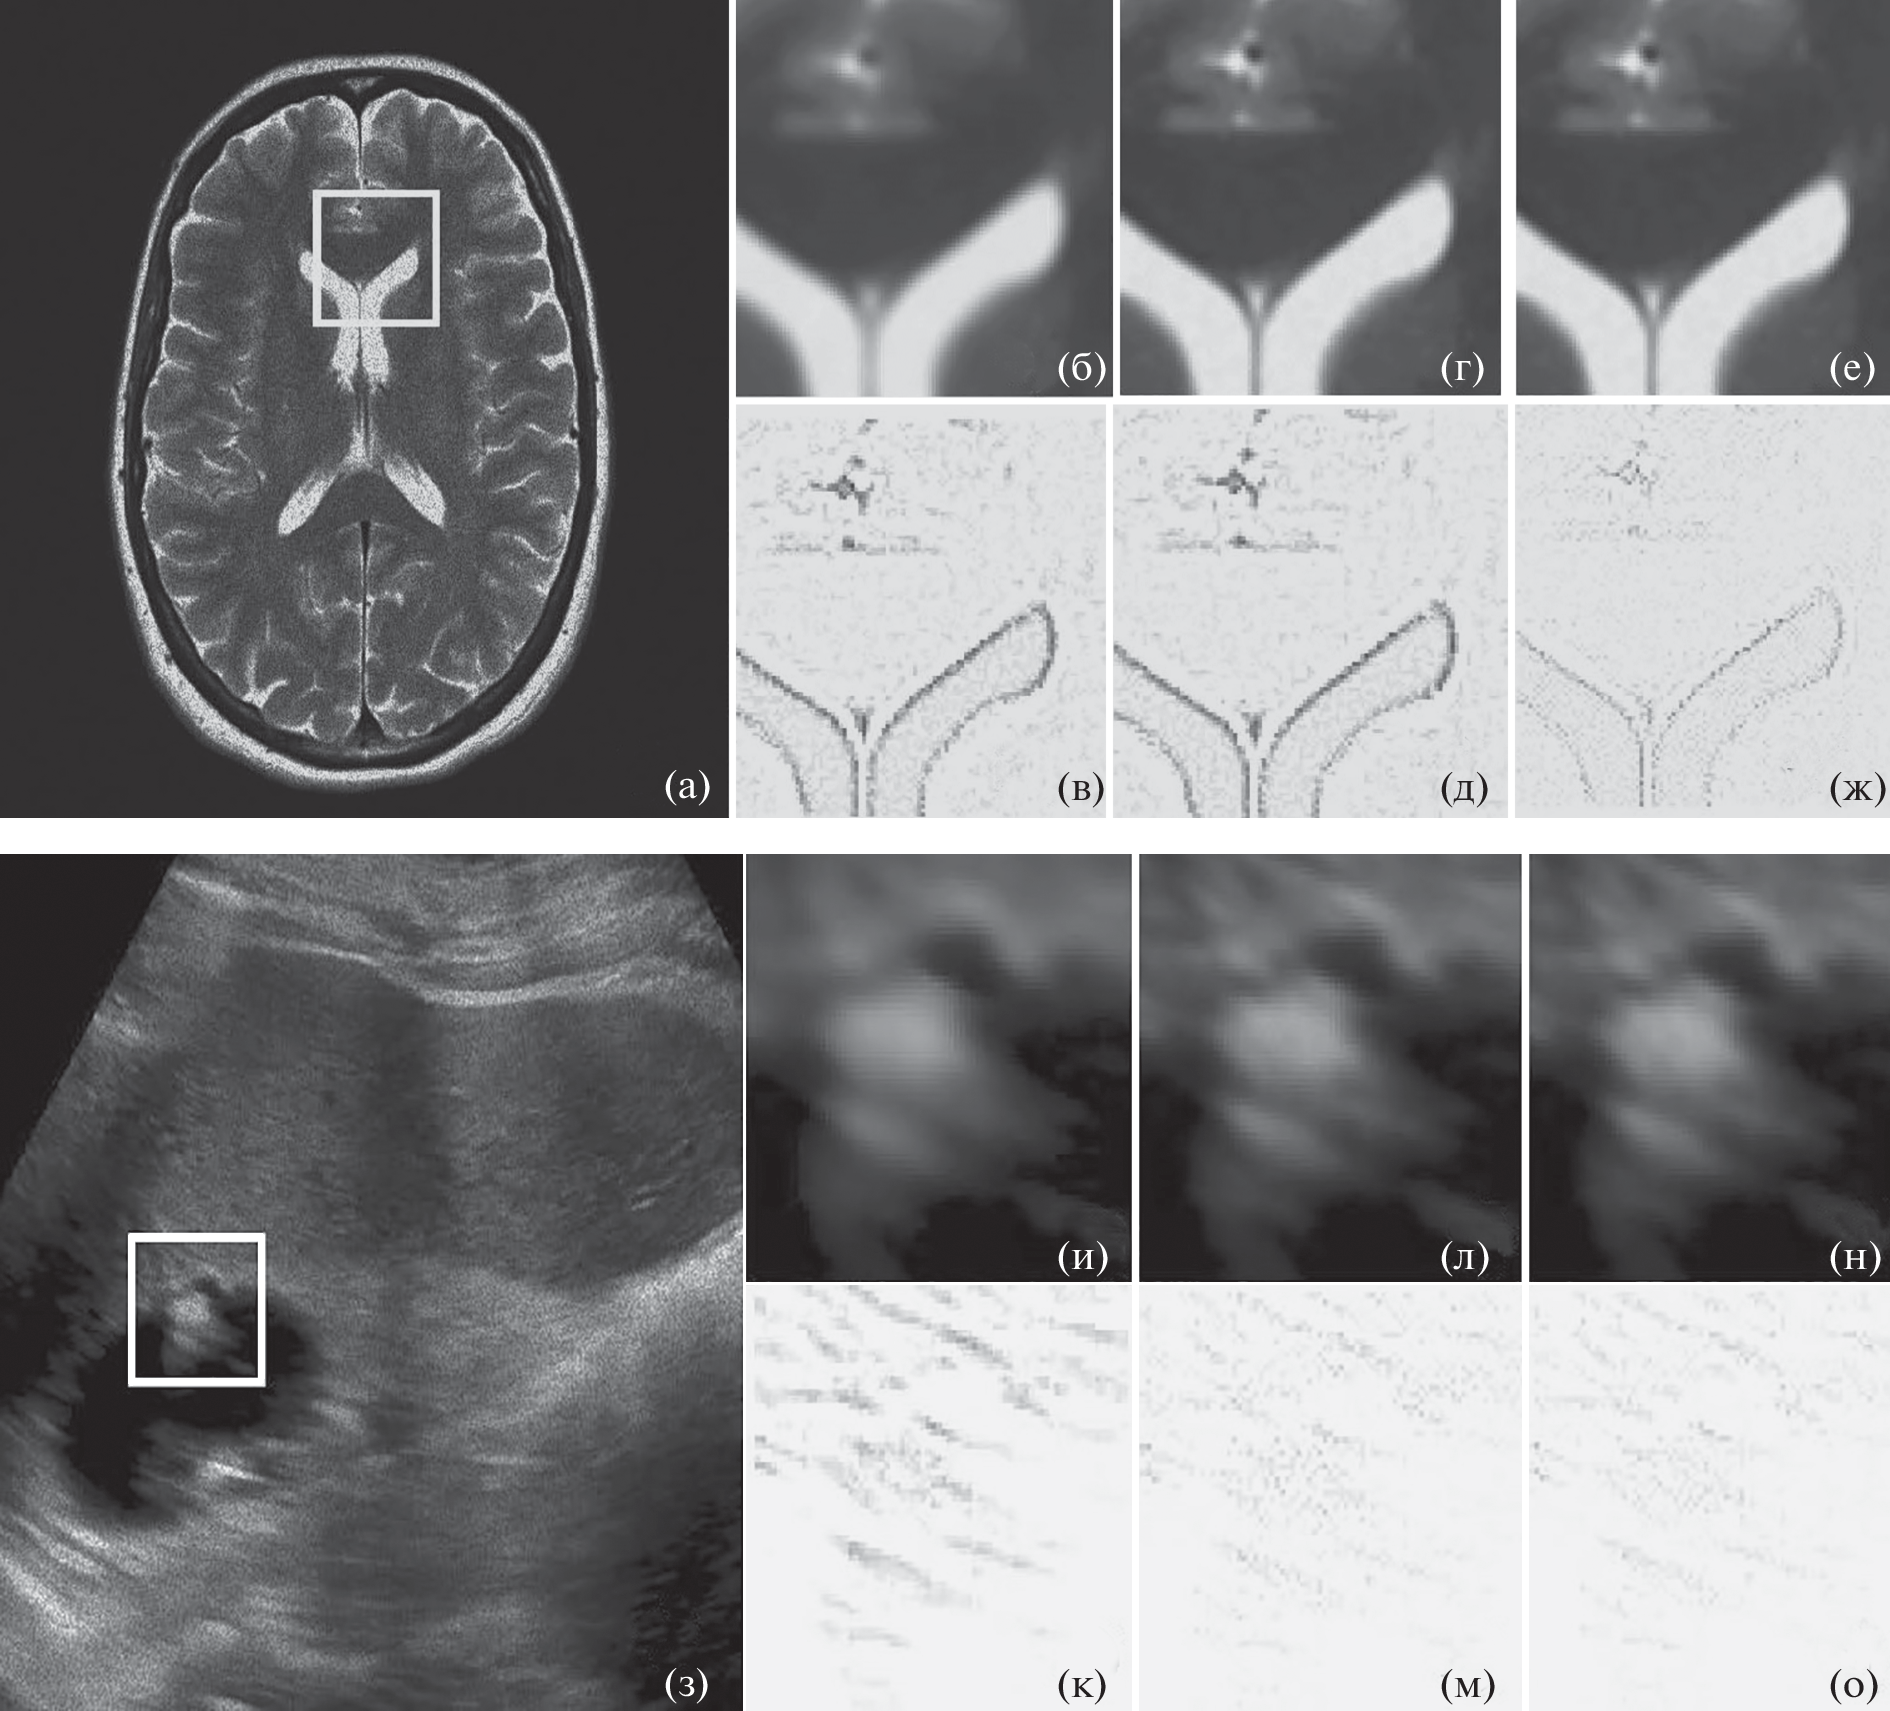

Novel filtering method in medical images (MRI and US) that are contaminated by noise consisting of mixture speckle and additive noise is designed in this paper. Proposed method consists of several stages: segmentation of image areas, grouping of similar 2D structures in accordance mutual information (MI) measure, homomorphic transformation, 3D filtering approach based on sparse representation in contourlet (CLT) space with posterior filtering in accordance with MI weights similar 2D structures, and final inverse homomorphic transformation. During numerous experiments, the developed method has confirmed their superiority in term of visual image quality via human visual perception as well as in better criteria values, such as PSNR, SSIM, EPI and alfa for different test MRI and US mages corrupted by speckle noise.